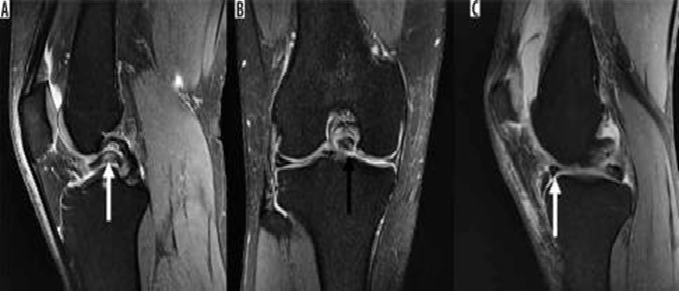

Hình 8. Nước mắt tay cầm xô lệch. A và B là hình ảnh cộng hưởng từ pd xóa mỡ với vết rách tay cầm cho thấy một mảnh sụn dịch chuyển liền kề với dây chằng chéo sau (mũi tên trắng), được gọi là dấu hiệu "dây chằng chéo sau đôi ", cũng như một mảnh sụn bị dịch chuyển trong rãnh liên chất (mũi tên đen). C là hình ảnh pd xóa mỡ với vết rách ở tay cầm cho thấy mảnh bị dịch chuyển ra phía trước (mũi tên trắng), tiếp giáp với sừng trước, được gọi là dấu hiệu "sừng trước kép".

Bác sĩ phẫu thuật có thể thực hiện cắt sụn một phần, cắt bỏ sụn chêm hoặc sửa chữa trực tiếp các vết rách sụn chêm. Tiêu chuẩn đánh giá rách sụn chêm sau phẫu thuật trở nên khó áp dụng vì hình dạng sau phẫu thuật của sụn chêm trùng với tiêu chuẩn chẩn đoán rách sụn chêm. Khi phẫu thuật cắt một phần khum, tín hiệu bất thường ban đầu là nội tạng bên trong sụn chêm có thể được chuyển thành tín hiệu chạm vào bề mặt trên hoặc bề mặt dưới. Mô hạt từ vết rách sụn chêm đang lành cũng có thể có các đặc điểm tín hiệu tương tự như vết rách. Do đó, việc chẩn đoán vết rách sụn chêm còn sót lại hoặc mới trong các trường hợp sau phẫu thuật dựa vào sự hiện diện của các mảnh sụn bị di lệch hoặc các nang thông số, hoặc sự hiện diện của cường độ tín hiệu dịch/gadolinium kéo dài vào sụn chêm (Hình 8)[8].